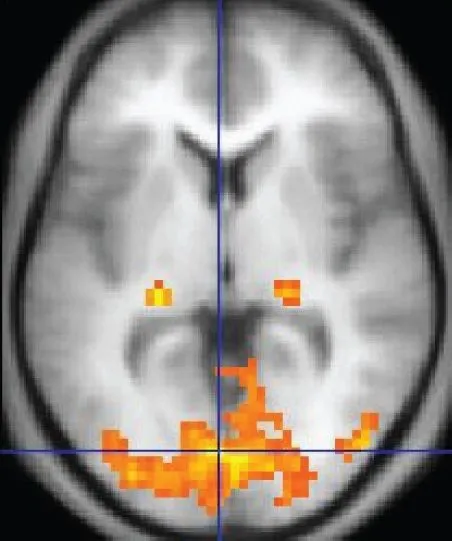

To understand where the neuronal signals are coming from, we need Functional Magnetic Resonance Imaging or fMRI. Unlike an EEG, fMRI does not measure the electrical impulses sent by the neurons, but rather records changes associated with the blood oxygenation in the brain.

An fMRI draws on the difference between the magnetic property of oxygenated and deoxygenated blood to create a map of the brain’s neuronal activity.

Deoxygenated blood causes more disruption in the local magnetic field than oxygenated blood, owing to its paramagnetic nature. When carrying out a specific task, the neuronal signaling increases in the corresponding region of the brain and receives increased levels of oxygenated blood.

Since oxyhemoglobin does not disrupt the local magnetic field, the fMRI can easily pick up on the changes in oxygenation which is then extrapolated to neuronal activity. It can pinpoint active areas of the brain with a 5mm accuracy.

fMRI can tell us which part of the brain is involved in various functions and study the effects of brain abnormalities, such as strokes or dementia.